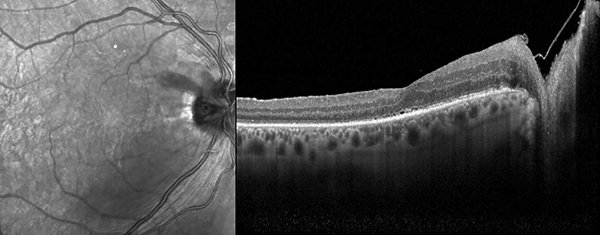

Examen oftalmológico postoperatorio mediato: AVMC OD 2/10, fondo de ojo derecho: pit de papila, atrofia peripapilar, fotocoagulación láser peripapilar y retina aplicada a nivel macular (figs. 8 y 9), y en OCT: retina aplicada con alteración de línea IS/OS (fig. 10).

Un mes después presentaba nuevamente disminución de la AV OD (1/10) y recidiva del desprendimiento seroso con retinosquisis en OCT. Mantuvimos conducta expectante y repetimos OCT a los siete días, donde observamos retina aplicada (fig. 11).

Figura 10. OCT postoperatoria de ojo derecho donde se aprecia reaplicación de la retina y posicionamiento del flap de membrana limitante interna sobre la papila.

Figura 11. OCT comparativa postoperatoria de ojo derecho. Se observa disminución del fluido subretinal y retinosquisis luego de recidiva de ambos.